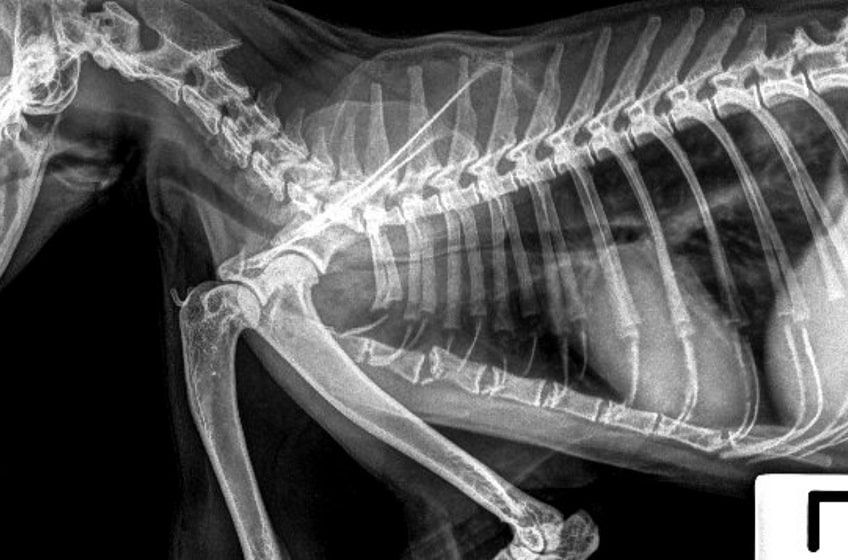

Po rozpoznaniu guza poiniekcyjnego należy wykonać badania obrazowe (RTG, USG, tomografię komputerową lub rezonans magnetyczny), by ocenić zasięg choroby oraz wykluczyć obecność przerzutów nowotworu do płuc i innych narządów kota. Następnie na podstawie lokalizacji i wielkości guza oraz ogólnego stanu pacjenta onkolog weterynaryjny dobiera schemat leczenia nowotworu.